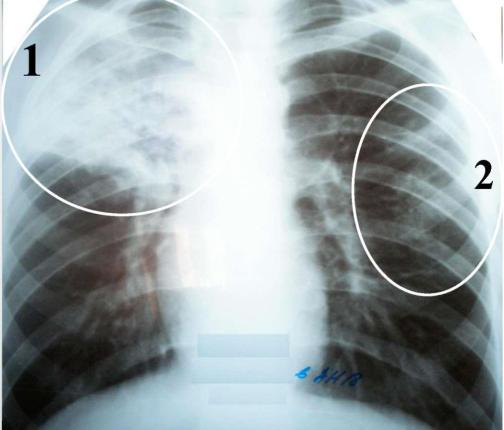

Симптомы и лечение инфильтративного туберкулеза легких

Раздел: Снимки-откровения